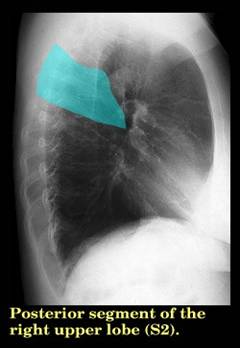

Анатомические изображения сегментов легких различных животных

Раздел: Другие животные